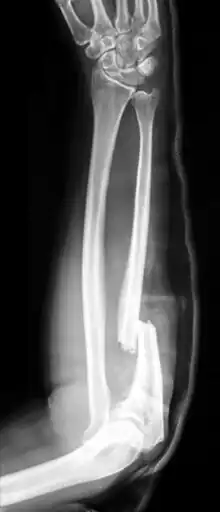

| Monteggia Fracture (type of ulna fracture) | |

- Monteggia fracture - a fracture of the near to elbow end of the ulna with the dislocation of the head of the radius at the elbow joint.[2]